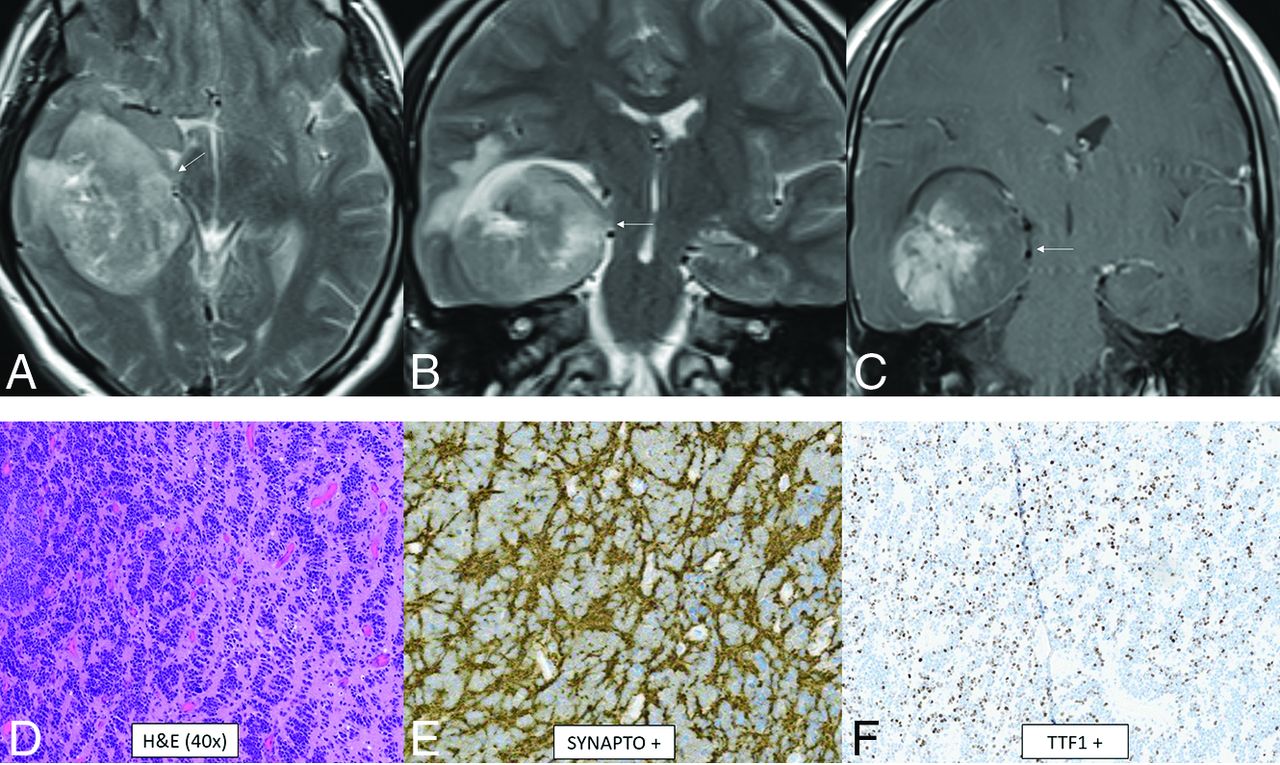

CNS neuroblastoma, FOXR2-activated. MR images show a large cortical and subcortical well-circumscribed expansile mass in the right temporal lobe involving the hippocampus (arrows) with T2-hyperintensity (A and B) and patchy enhancement (C). Histology shows a highly cellular infiltrating neuroepithelial neoplasm with a complex pattern, including an undifferentiated and extensive spongioblastoma pattern with brisk mitotic activity (D). On immunohistochemistry, the tumor shows divergent differentiation with expression of synaptophysin (E), OLIG2, and TTF1 (F). Whole-genome methylation profiling indicated a match to CNS neuroblastoma, FOXR2-activated.

CNS neuroblastoma is a highly malignant embryonal tumor without an official WHO grade. These tumors have variable chromosomal rearrangements or mitochondrial DNA insertions converging on FOXR2, leading to overexpression.67,68 FOXR2 binds to and stabilizes MYC and MYCN proteins and therefore promotes MYC-related transcriptional activities, leading to increased cellular proliferation and tumorigenesis.67,68 Histology shows a small-cell tumor, embryonal architecture, a high proportion of neuropil, neurocytic cell, or ganglion cell differentiation, and, frequently, vascular pseudorosettes and nuclear palisades.67 OLIG2 and synaptophysin are positive.67 The median age is 4.5 years (range, 1.4–16 years) without a sex predilection.69 In the largest described series, tumors were large and supratentorial with invariable involvement of the deep white matter and frequent invasion of the cortex (80%) as well as a ventricular ependymal surface (64%).69 The frontal lobe was the most common location, though involvement of multiple regions was common. Typical tumors were multilobulated, solid, and cystic/necrotic, T2-hyperintense, enhancing, and diffusion-restricting (Fig 10). Calcification or hemorrhage was present in approximately 40% of tumors. Calvarial remodeling was present in nearly half of cases and occurred more frequently with larger tumors.